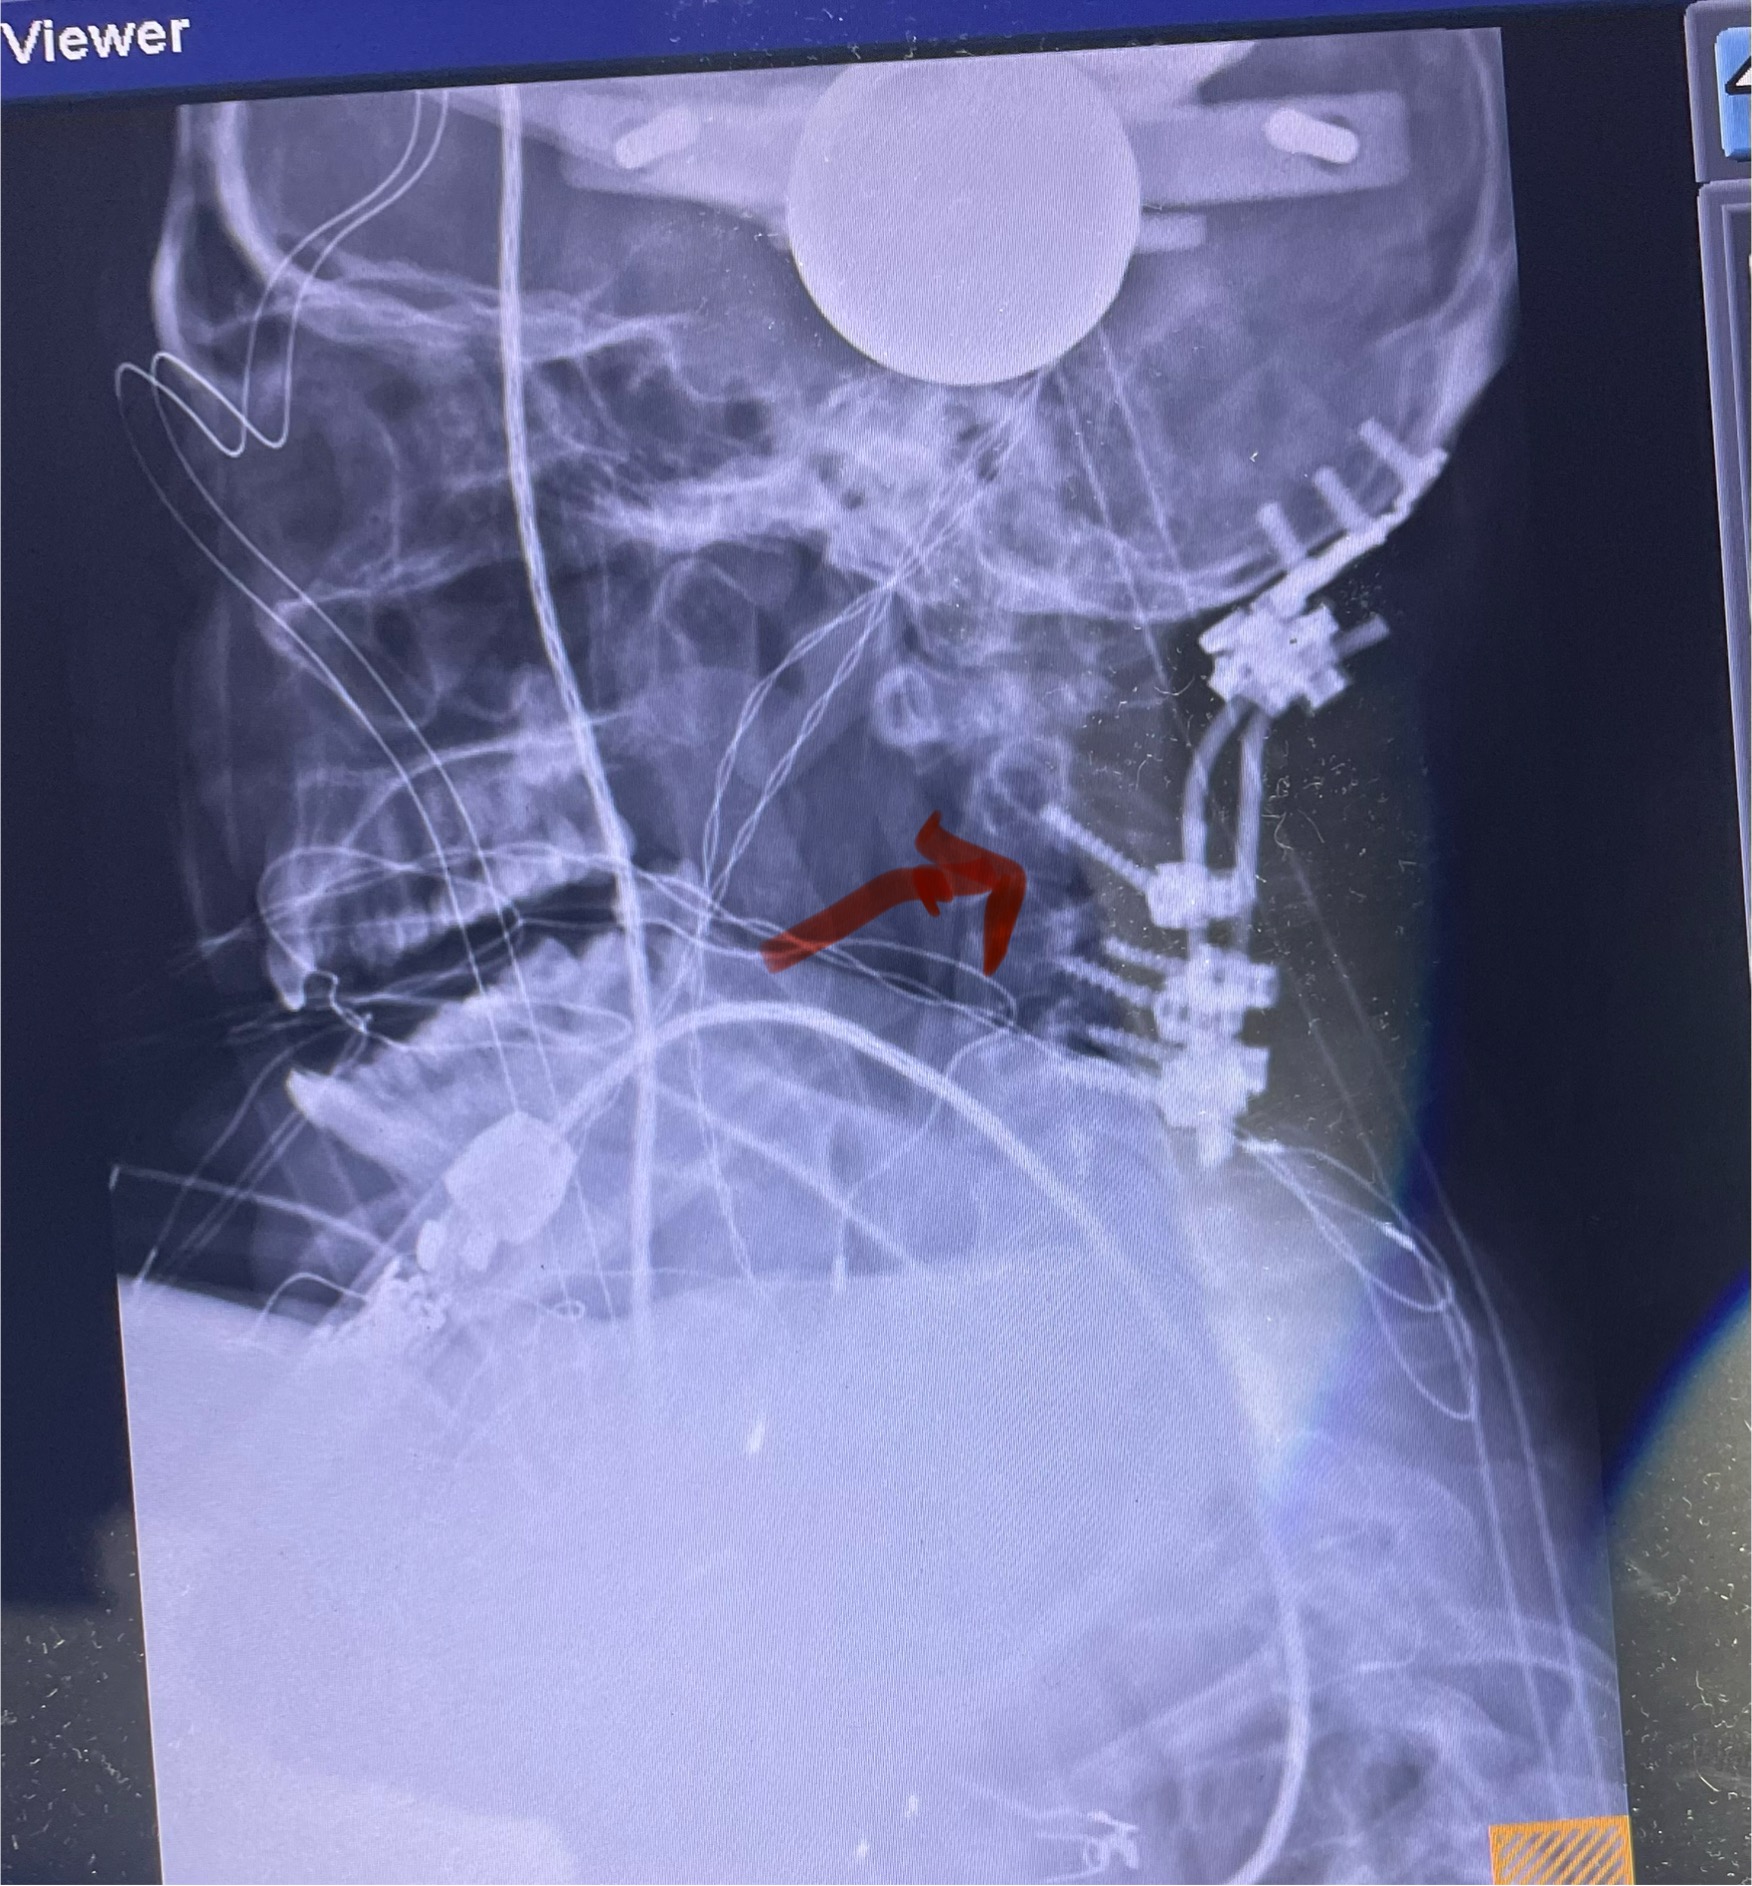

Clearly this explained her right upper extremity symptoms. Because of her weakness, it was decided to perform an anterior cervical discectomy at C5-6 and C6-7 and interbody fusion with plate. An extruded disc was found at C6-7. The patient did well postoperatively with improvement of her radiating pain and strength (Fig 3). This case illustrates the importance of repeating an MRI if the symptoms and signs do not correlate with the MRI findings. Disc herniations can change. They can be reabsorbed, and they can also worsen over time.

Fig 3: Intraoperative lateral cervical x-ray demonstrating good placement of the C5-C7 interbody cages and plate (red arrow)